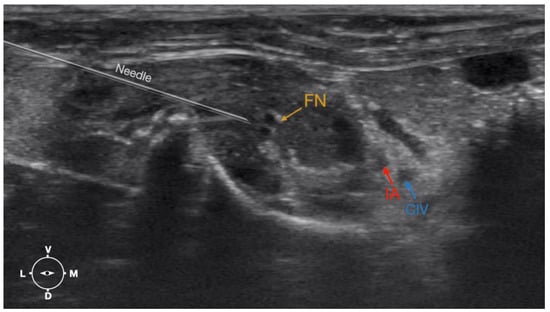

Figure 6. Ultrasonographic image demonstrating the approach of the needle towards the femoral nerve. The window of interest was set at a depth of 2 cm and the focus was at the level of the femoral nerve to optimize the image quality. IA, iliac artery, CIV, common iliac vein; FN, femoral nerve; D, dorsal; L, lateral; M, medial; V, ventral.

2.3.2. Femoral Nerve Injection

The cadaver was positioned in dorsal recumbency before the leg was extended caudally. The transducer was placed over the hypaxial muscles, transverse to the long axis of the spine, and at the level of the projection of the iliac crest. The window of interest was set at a depth of 2 cm to optimize the image. Then, the transducer was moved in caudal direction along the IPM until the femoral nerve was clearly seen in the substance of the IPM (Figure 4). A 50 mm 22-gauge insulated needle (Sonoplex Stim Cannula, Pajunk Medical Produkte GmbH, Germany) prefilled with a L-NMB solution was inserted using an in-plane approach. The needle was inserted at the lateral edge of the transducer and advanced in-plane under sonographic guidance through the iliac fascia and IPM in a dorso-medial direction towards the femoral nerve (Figure 5 and Figure 6). The needle was advanced until its tip was located in vicinity of the femoral nerve. A test volume of 0.05 mL of L-NMB was injected to confirm adequate distribution. The remaining volume of 0.15 mL/kg was then injected extraepineurally around the femoral nerve.